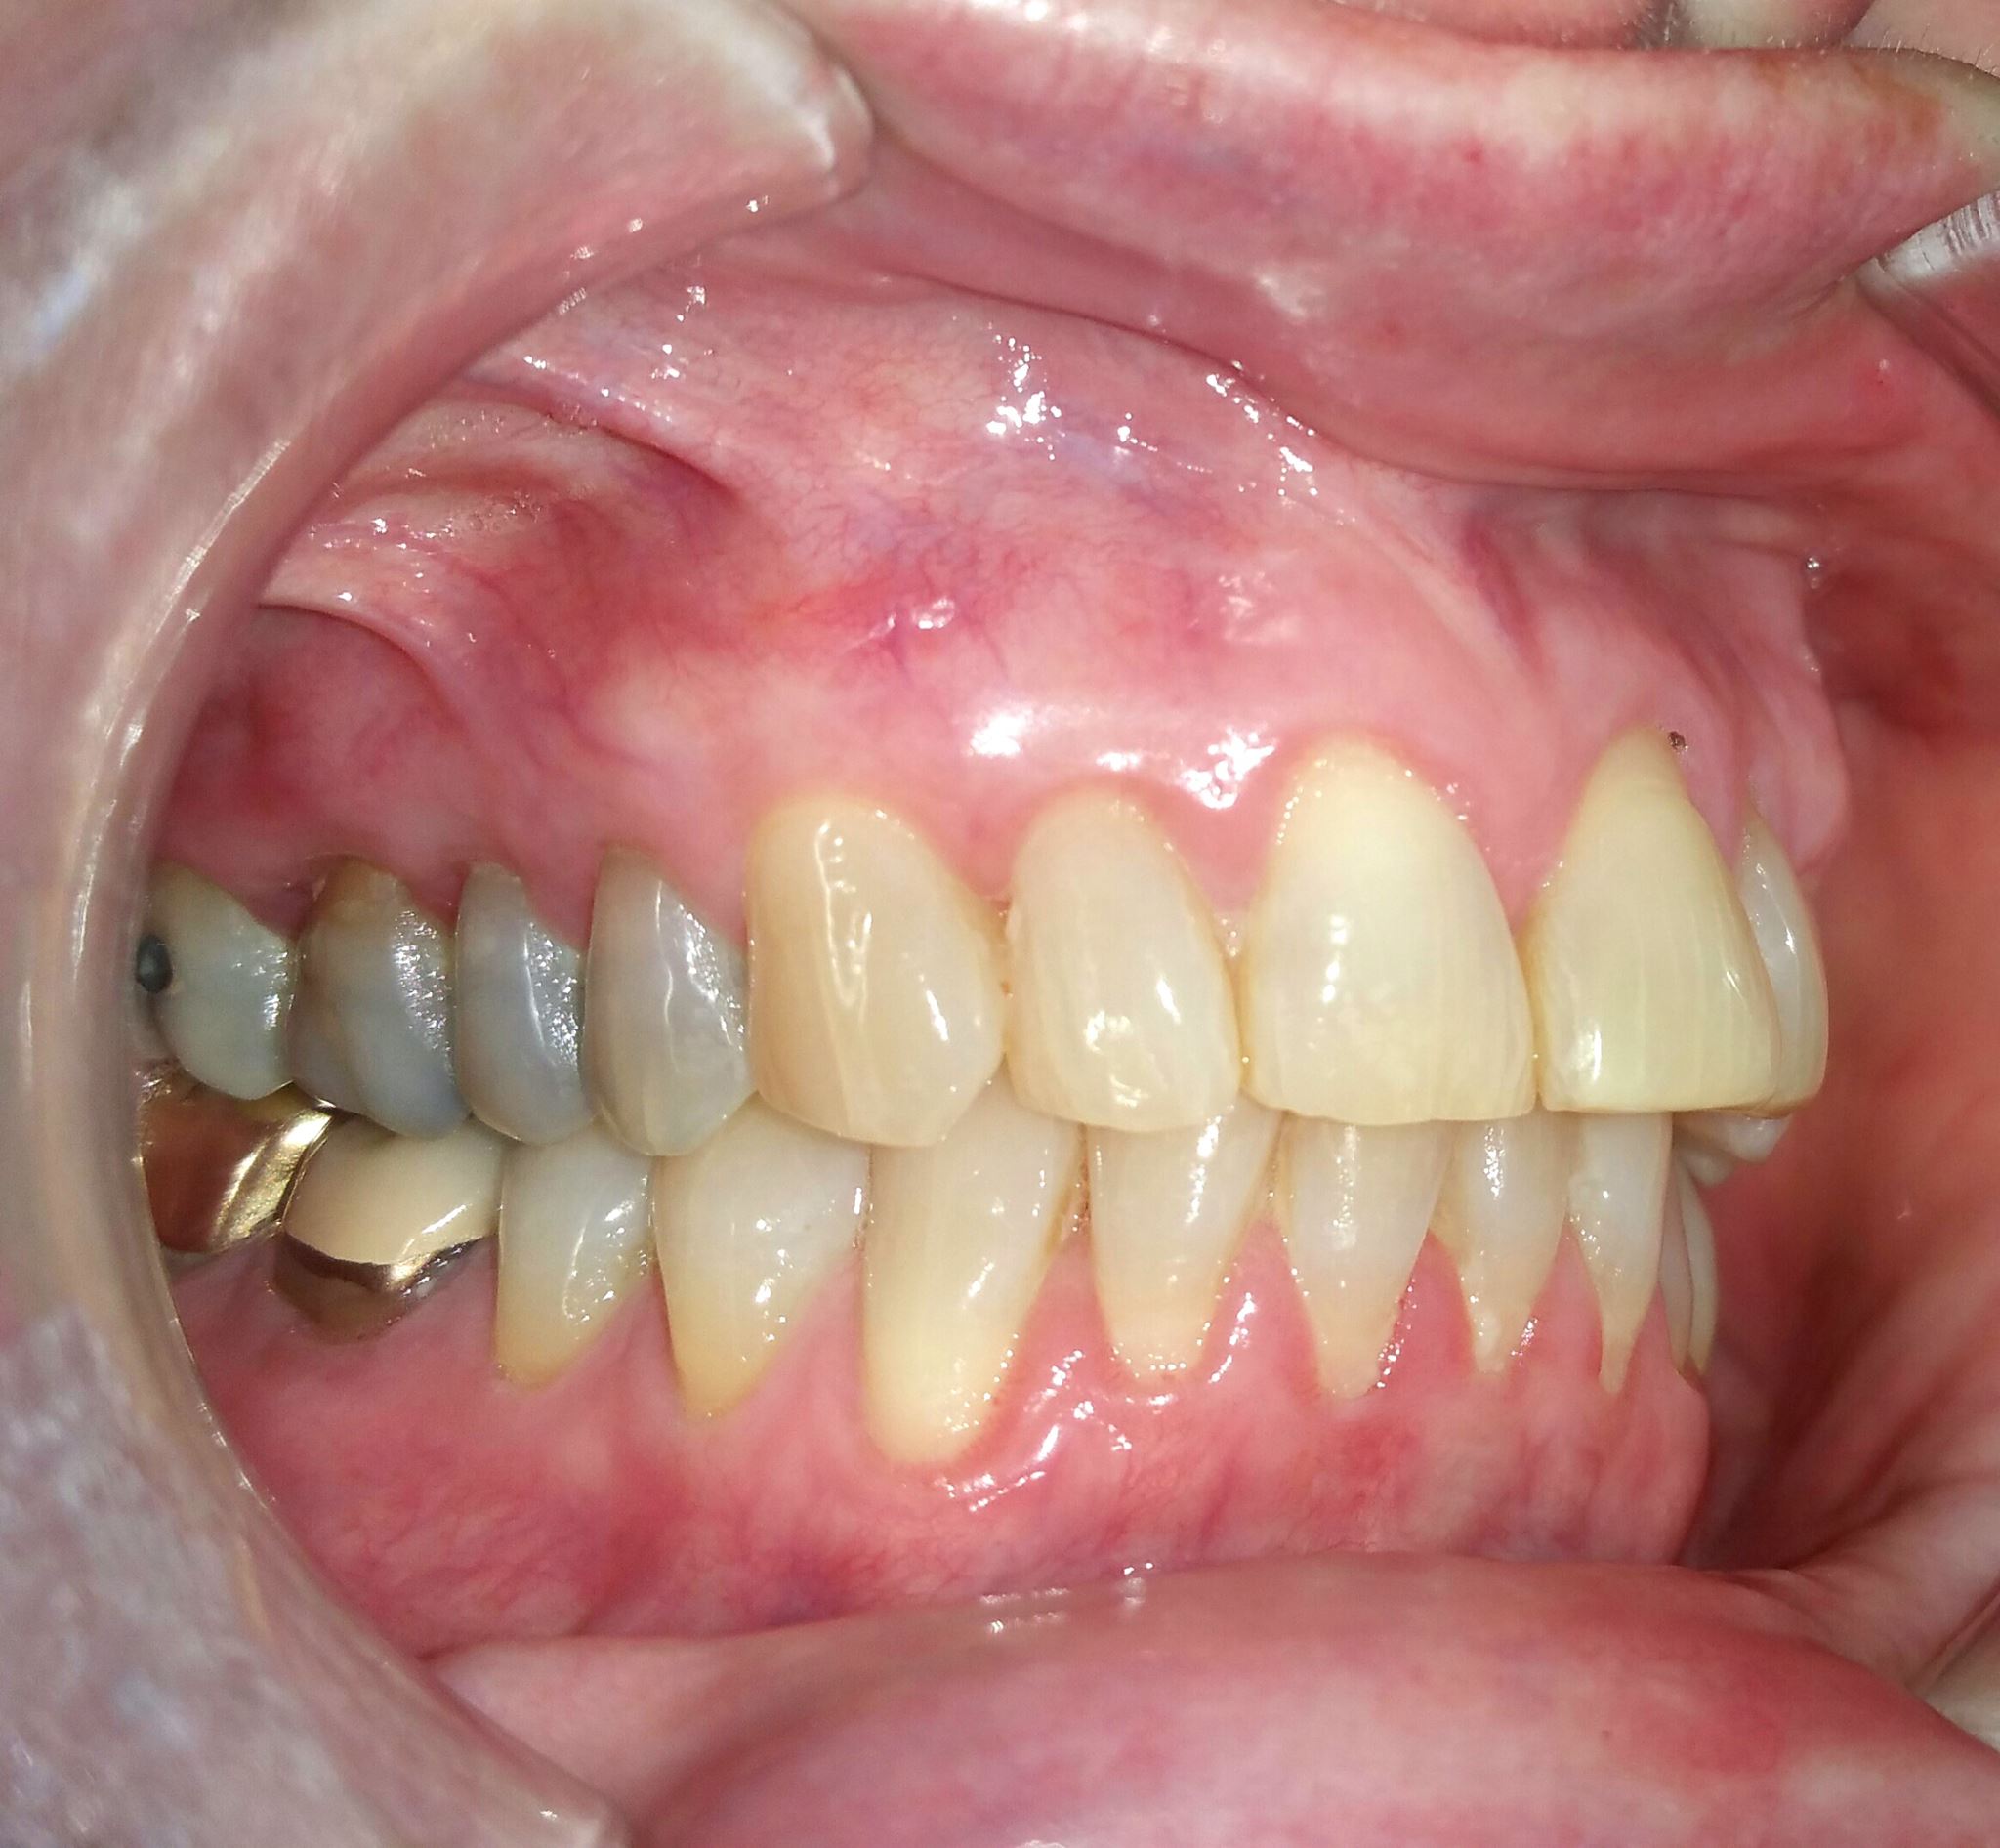

BEFORE AND AFTER PICTURES: